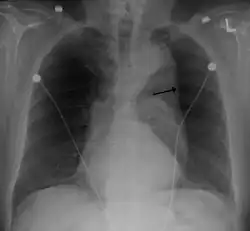

A thoracic aortic aneurysm is an aortic aneurysm that presents primarily in the thorax.

A thoracic aortic aneurysm is the "ballooning" of the upper aspect of the aorta, above the diaphragm. Untreated or unrecognized they can be fatal due to dissection or "popping" of the aneurysm leading to nearly instant death. Thoracic aneurysms are less common than an abdominal aortic aneurysm.[2] However, a syphilitic aneurysm is more likely to be a thoracic aortic aneurysm than an abdominal aortic aneurysm. This condition is commonly treated via a specialized multidisciplinary approach with both vascular surgeons and cardiac surgeons.

Diagnosis

Thoracic aortic aneurysm is defined as a cross-sectional diameter exceeding the following cutoff:

A diameter of 3.5 cm is generally considered dilated.[7] However, average values vary with age and size of the reference population, as well as different segments of the aorta.